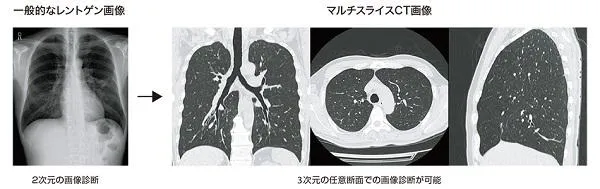

マルチスライスCT装置

通常のX線撮影と異なり、多断面画像が撮影されるため、内部構造を詳しく診断することができます。 また、簡易性・迅速性・無痛性の点でも優れた特徴を有しております。頭部・胸部・上腹部・下腹部などを検査し、病変を早期発見します。 撮影した写真は当院医師の他に、月に一度、専門の医師もよる診断も行っています。